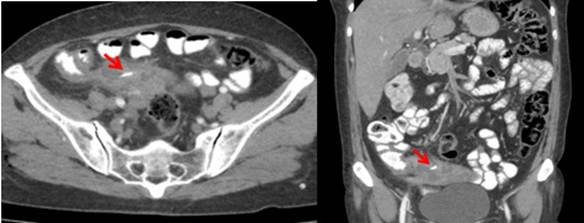

Paciente de 65 años con dolor abdominal tipo cólico localizado en la región inguinal derecha, irradiado al flanco y región lumbar ipsilateral. Se realizó una tomografía computarizada contrastada observando un marcado engrosamiento del apéndice cecal, perdida de su configuración y una colección heterogénea multiloculada con una imagen hiperdensa lineal de aproximadamente 18 mm en su interior, sugestiva de cuerpo extraño, hallazgos compatibles con apendicitis aguda, perforación contenida y formación de absceso periapendicular (figura 1).